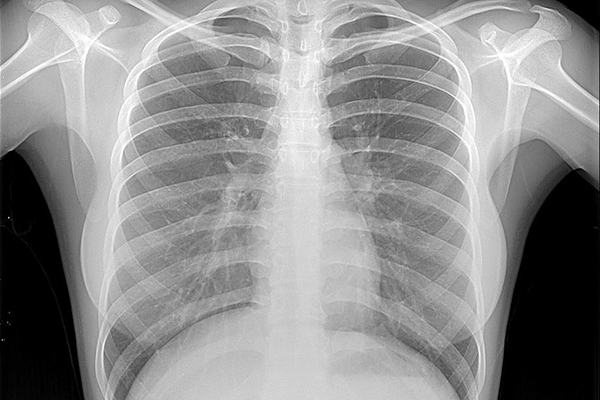

В Республике Молдова увеличивается число случаев заболевания тяжелыми формами туберкулеза, в том числе с развитием устойчивости к антибиотикам. В беседе с корреспондентом IPN директор Муниципальной клинической больницы фтизиопневмологии Мария Четулян сообщила, что годовой показатель смертности в результате этого заболевания составляет 12 человек на 100 тысяч населения. В муниципии Кишинэу на учете состоят 1200 больных туберкулезом граждан, однако реальное количество больных больше, учитывая, что некоторые инфицированные люди не обращаются к врачу.

Туберкулез распространяется воздушно-капельным путем, заразиться можно от кашляющего или чихающего больного. Предрасположенность к инфицированию есть у людей с низким иммунитетом и с хроническими заболеваниями – гепатитом, сахарным диабетом, болезнями эндокринной системы. Выше риск заболеть туберкулезом у граждан, которые живут в перенаселенной среде, работают в больницах, приютах для бездомных, в подземных помещениях, казармах и пенитенциарных учреждениях. За последние годы выросло число больных среди граждан, злоупотребляющих алкоголем, употребляющих наркотические вещества, работающих в условиях повышенной влажности. Если в семье кто-то болен туберкулезом, остальные члены семьи могут также заболеть.

Методом предупреждения заболевания является вакцинация. "Вакцинированный человек, даже если и заболеет туберкулезом, то в более легкой форме", - говорит директор Муниципальной клинической больницы фтизиопневмологии. На этой неделе в муниципии Кишинэу проводятся мероприятия по информированию о туберкулезе и по продвижению здорового образа жизни. В 2012 году в Республике Молдова было зарегистрировано около 4000 новых случаев туберкулеза.

Согласно сообщению для прессы Центра развития в области здравоохранения „Afi”, ежегодно в мире заражаются туберкулезом 8 миллионов человек. Каждые четыре секунды появляется новый случай туберкулеза. Каждые две минуты от туберкулеза умирает ребенок. Каждый больной способен инфицировать 10-15 человек. В наибольшей степени подвержены заболеванию члены семьи, родственники и друзья больного.